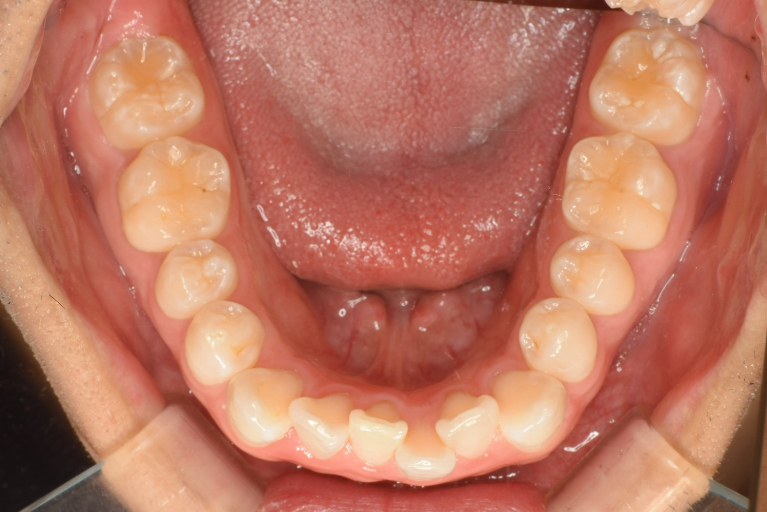

術前

術中

術後

| 治療名 | インビザライン・ライトによる前歯のガタつき改善症例 |

| 治療説明 | 前歯のガタつき(叢生)をマウスピース型矯正装置「インビザライン・ライト」で改善した症例です。 全体的な咬み合わせには大きな問題がなかったため、短期間で前歯の並びを整えることができました。ワイヤーを使わず、透明なマウスピースで目立たずに治療を行いました。 |

| 治療回数・期間 | 約4ヶ月 |

| 副作用とリスク | ・インビザライン矯正では、1日20時間以上のマウスピース装着が必要です。 ・歯の移動に伴って、痛みや咬合時の違和感が生じることがあります。 ・歯ぐきが下がる(歯肉退縮)や、歯の根が短くなる(歯根吸収)などの可能性があります。 ・使用できるマウスピースの枚数に制限があるため、すべての症例に適応できるわけではありません。 |

| 料金(税込) | 770,000円 |